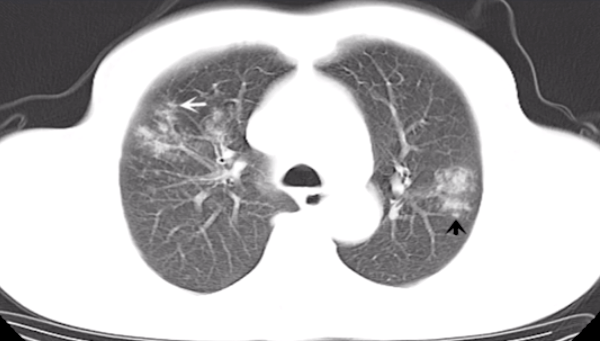

第三题:如下图所示 , 病变表现为双肺多发斑片、磨玻璃影 。 可见小叶中心结节、树芽征 。

文章图片

【识别|肺部 CT 秒杀:快速识别各类影像】第三题答案: 金黄色葡萄球菌肺炎 , 常表现为小叶性肺炎 。